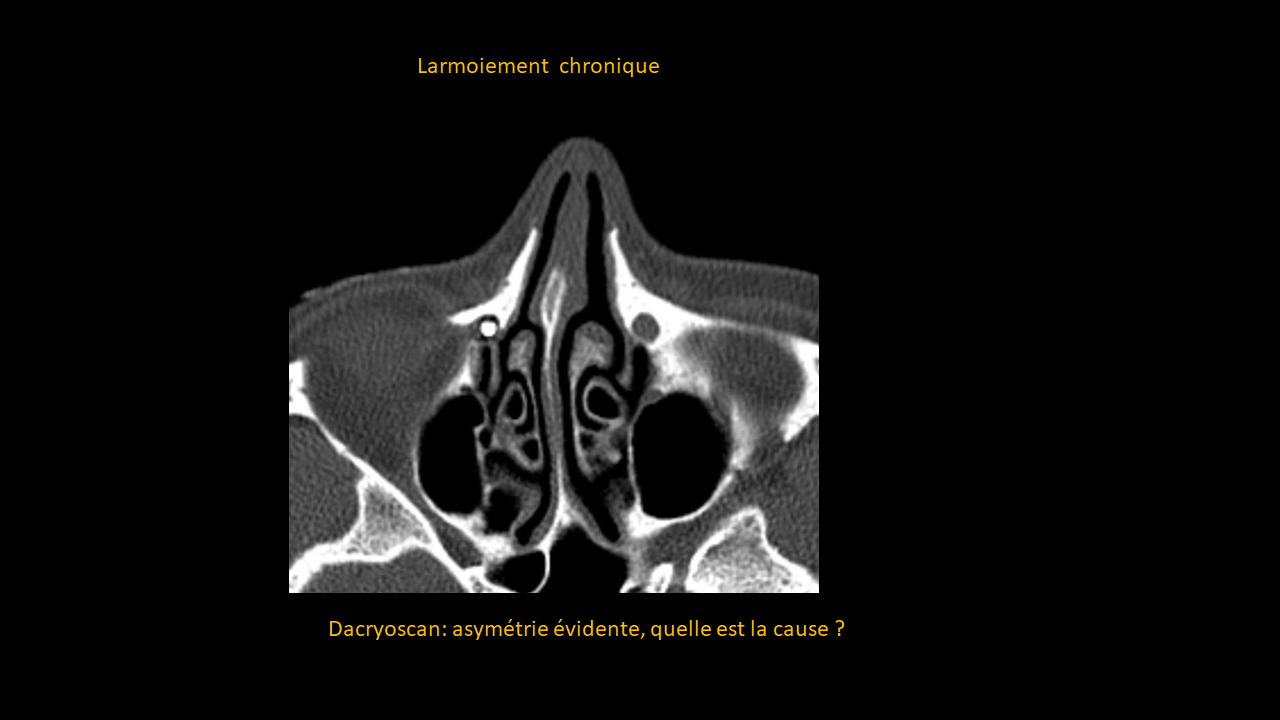

Dacryoscanner